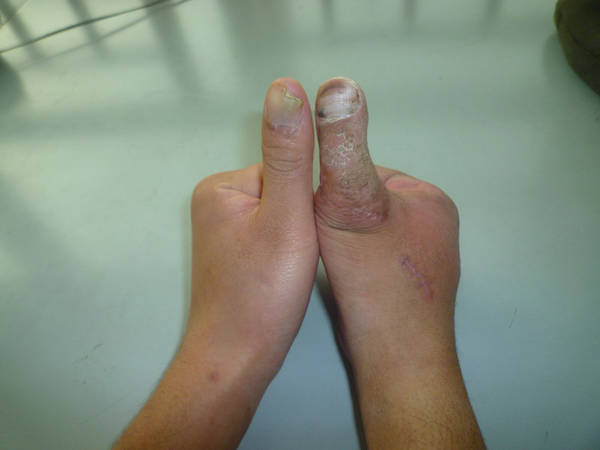

[手指再造] 拇再造术后供区的另一种修复(12.23随访照片来了)

1.jpg 2.jpg 3.jpg 4.jpg 5.jpg 6.jpg 7.jpg 8.jpg 9.jpg 10.jpg 11.jpg 12.jpg 13.jpg

功能和外观都很好,学习了,池主任的病人应该感到幸运和幸福